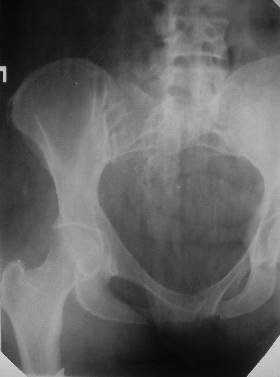

Уважаемые коллеги! Хотел-бы обсудить интерессный, на мой взгляд, случай.На консультацию пришла женщина 45 лет с отводящей контрактурой правого бедра.

Из анамнеза: в ноябре 2002г. оступилась,упалана трап самолета (на верхней площадке, сразу при выходе из салона) на правый тазобедренный сустав, а затем - вниз на землю на ноги и ягодицы. Потеряла сознание от боли. Доставлена в больницу по месту жительства, лечилась консервативно с диагнозом кокцигодиния.На рентгенограмме от 27.11.02г. вывиха копчика не определяется (снимок идентичен представленной R-грамме от28.11.03г., кроме этого есть нормальная R-грамма копчика в боковой проекции).Через три недели стала ходить, но привести правую ногу в тазобедренном суставе не могла. Сейчас ходит отведя кнаружи правое бедро и голень, как ножку циркуля (фото 1). Неврологических нарушений нет. По просьбе врачаможет на 30-40 секунд поставить ноги вместе (фото 2). При этом испытывает сильную тянущую боль и ощущение "вывернутости" в правом тазобедренном суставе. Эти ощущения заставляют вновь отвести бедро. В положении лежа разогнуть бедро полностью не может из-за болей в ягодичной мышце (фото 3). Сгибание также ограничено из-за болей (фото 4). Отведение в положении лежа возможно в том же объеме, что и стоя (фото 5). Заподозрен старый разрыв правого крестцово-подвздошного сочленения.Выполнено R-исследование и КТ(в приложении). По-поводу деформации лонного сочленения выяснен гинекологический анамнез. Роды одни, нормальные в 22 года. Из роддома выписана на 8 сутки, нарушения походки не было, R-графия таза не проводилась. Вопросы на обсуждение: 1. Диагноз либо алгоритм дальнейшего обследования. 2. Лечебная тактика (в первую очередь возможность и целесообразность оперативного лечения).

Уважаемый Юрий Алексеевич, сделаны ли пациентке более дистальные срезы КТ с захватом области тазобедренного сустава? Учитывая давность травмы, могли присоединиться и дистрофические процессы в субхондральной кости головки и впадины. Изменения в капсуле будут хорошо видны на УЗИ, особенно в сравнении со здоровой стороной. Эффективность лечебно-диагностического введения гормональных препаратов, на мой взгляд, сомнительна ввиду давности патологического состояния. При такой стойкой и давней контрактуре без операции вряд ли можно обойтись. Под наркозом амплитуда на разгибание должна увеличиться, усилить эффект можно тено-миотомиями заинтересованных групп мышц, капсулотомией + в послеоперационном периоде хорошее консервативное противовоспатлительное лечение с укладками на разгибание.Что мешает приведению пока не ясно, во встретившихся в нашей работе аналогичных ситуациях причиной был формирующийся медиальный остеофит головки, выталкивающий её из впадины.